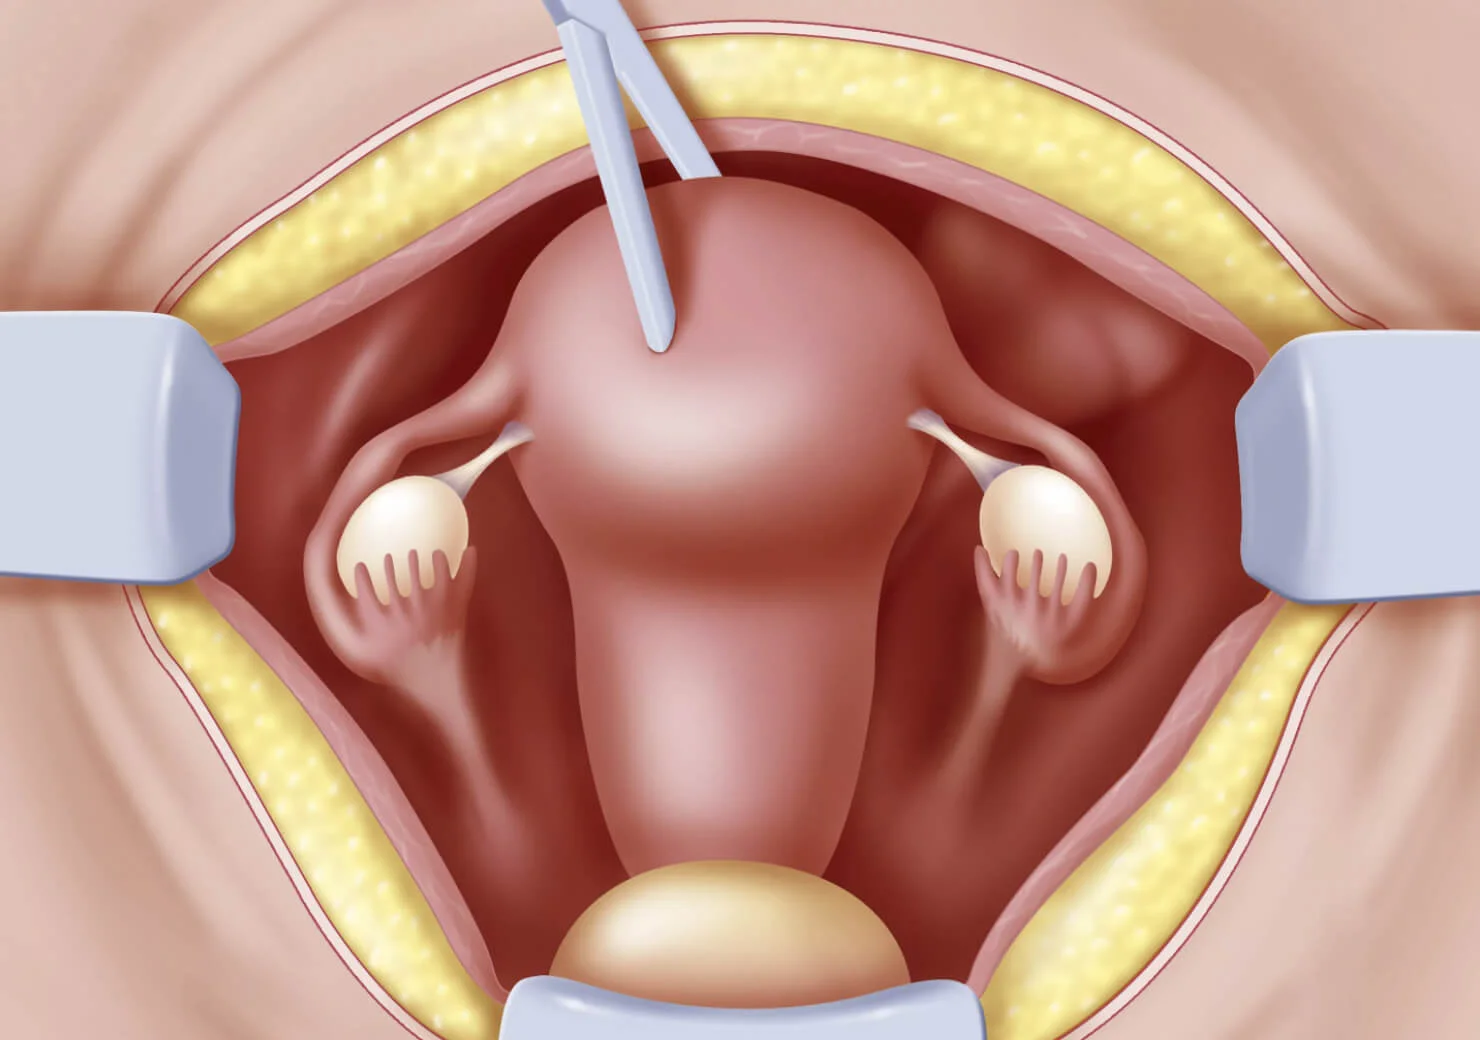

- Histerectomía

- Ooforectomia